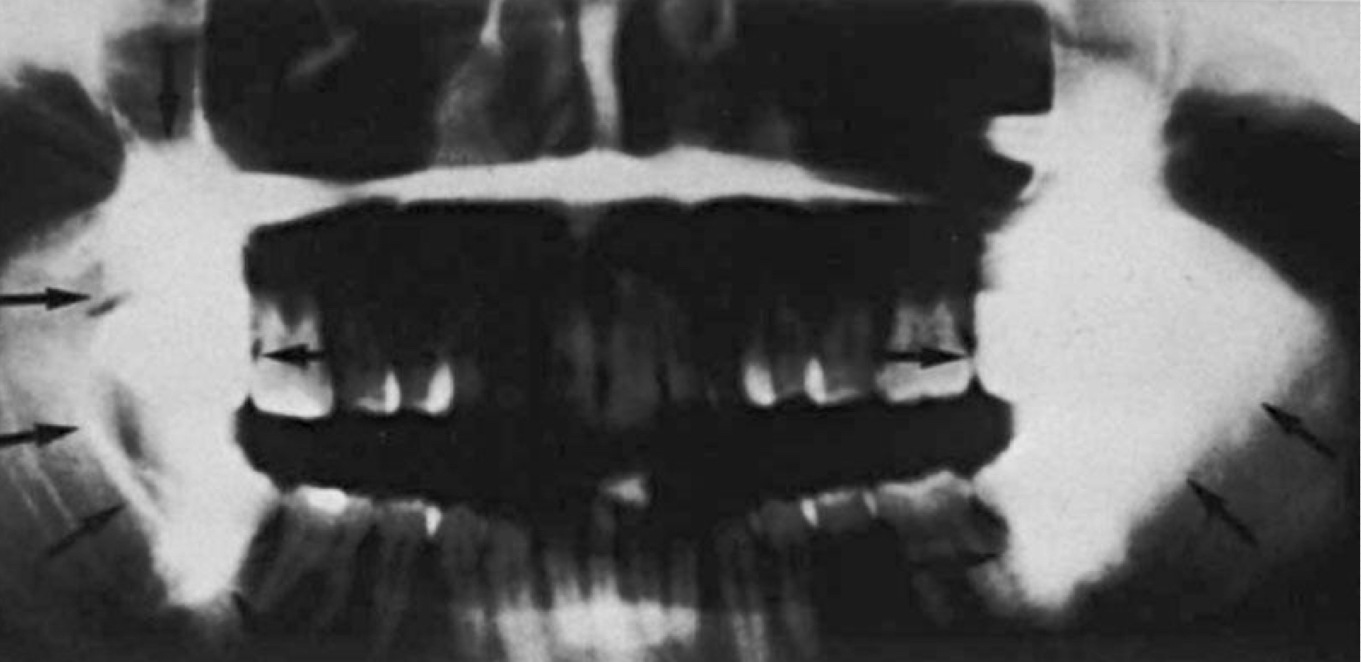

Amalgam restorations

Amalgam fragments

Gold :

Porcelain-fused-to-metal crown (PFM)

PFM bridge

Composite restorations

MOD

Acrylic denture

Base material

Metallic pins

Gutta percha

Silver points

Unloaded implant

Implant loaded

Removable partial denture

Earrings

Nose ring